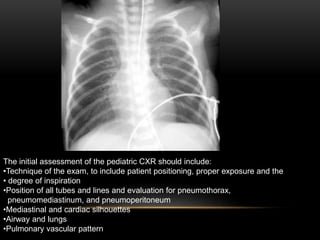

The initial assessment of the pediatric CXR should include:

•Technique of the exam, to include patient positioning, proper exposure and the

• degree of inspiration

•Position of all tubes and lines and evaluation for pneumothorax,

pneumomediastinum, and pneumoperitoneum

•Mediastinal and cardiac silhouettes

•Airway and lungs

•Pulmonary vascular pattern